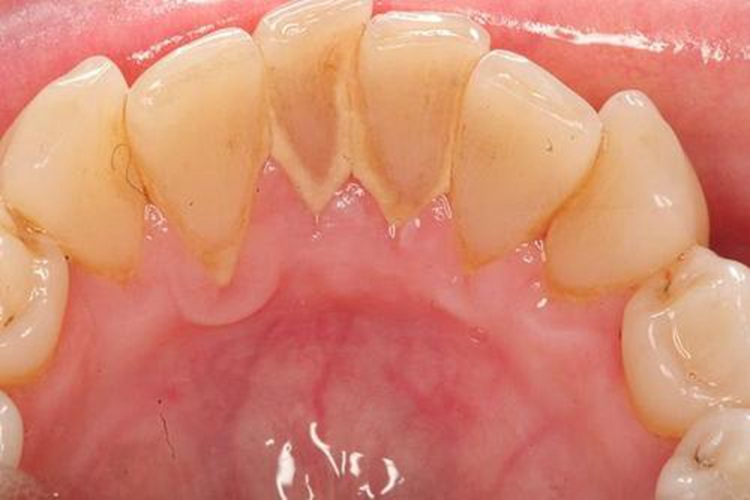

牙周炎早期不止有三大症状,一般表现为牙龈的慢性炎症,患者可有刷牙或进食时牙龈出血或口内有异味,但一般无明显不适。部分患者还可表现为少量黄色或褐色牙菌斑、牙石,以及深牙周袋的形成。

牙周炎的病因主要为牙菌斑,牙石、食物嵌塞、不良修复体等均为加重菌斑滞留的局部刺激因素。部分患者发病可能是由伴放线聚集杆菌侵袭牙周所致。